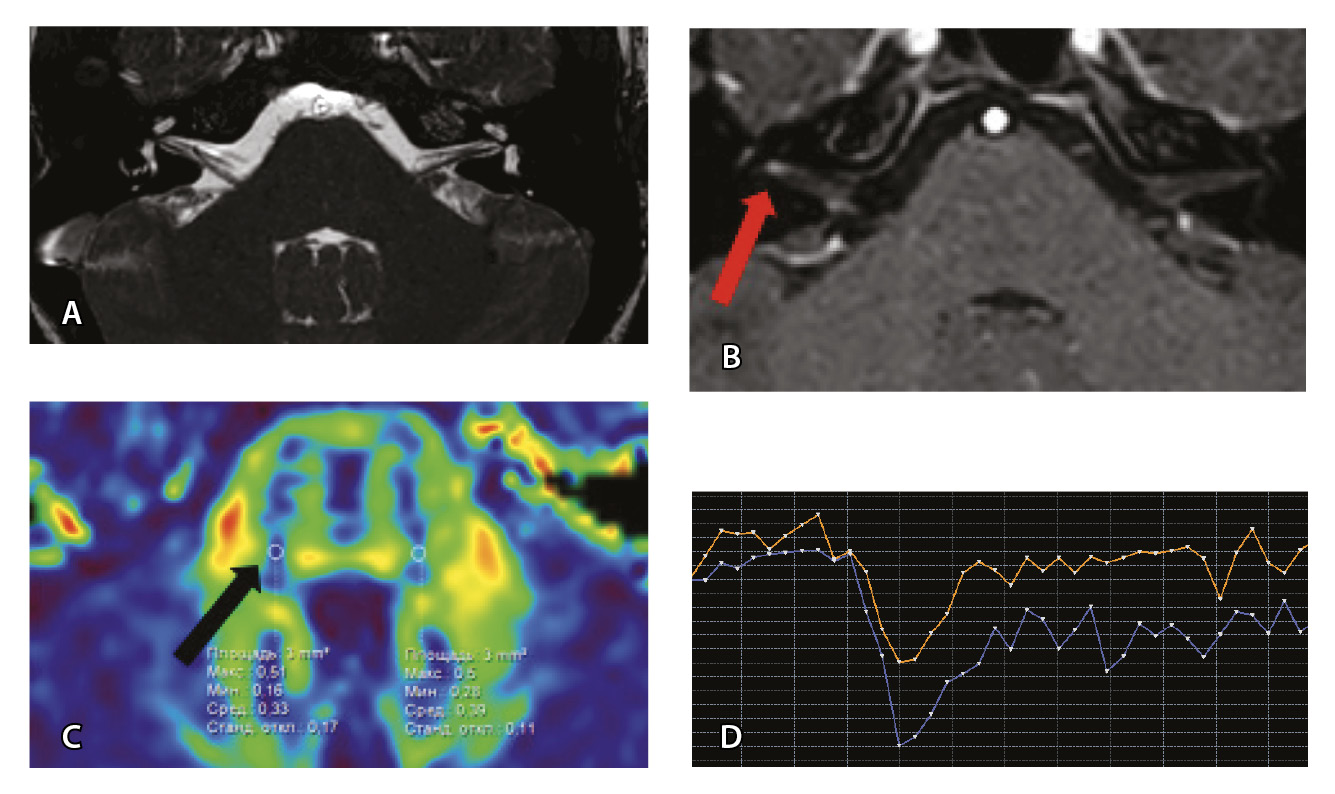

Проведена МП-МРТ головного мозга и черепно-мозговых нервов. Заключение: МР-признаки локального участка повышенного накопления контрастного вещества правым ЛН во внутреннем слуховом проходе – изменения могут соответствовать невриту ЛН (рис. 6).

Рис. 6. Пациентка З. Магнитно-резонансная томография (МРТ) головного мозга: А – прицельная T2-SSFP на область мосто-мозжечкового угла; Б – Т1-взвешенное изображение с контрастным усилением; В – диффузионно-тензорная МРТ (фракционная анизотропия, ФА); Г – Т2*-перфузия. На изображении T2-SSFP патологические изменения на уровне прохождения лицевых нервов во внутренних слуховых проходах не определяются (А). При контрастировании отмечается накопление контрастного вещества правым лицевым нервом во внутреннем слуховом проходе (Б, красная стрелка). На уровне моторных ядер лицевого нерва в заднем отделе варолиевого моста на изображениях ФА на стороне поражения отмечается минимальное уменьшение показателя ФА до 0,33 (В, черная стрелка) и признаки гипоперфузии справа (Г, оранжевый график) по сравнению с контралатеральной стороной (Г, синий график). Данный пример демонстрирует типичные изменения при мультипараметрической МРТ у пациента с параличом Белла